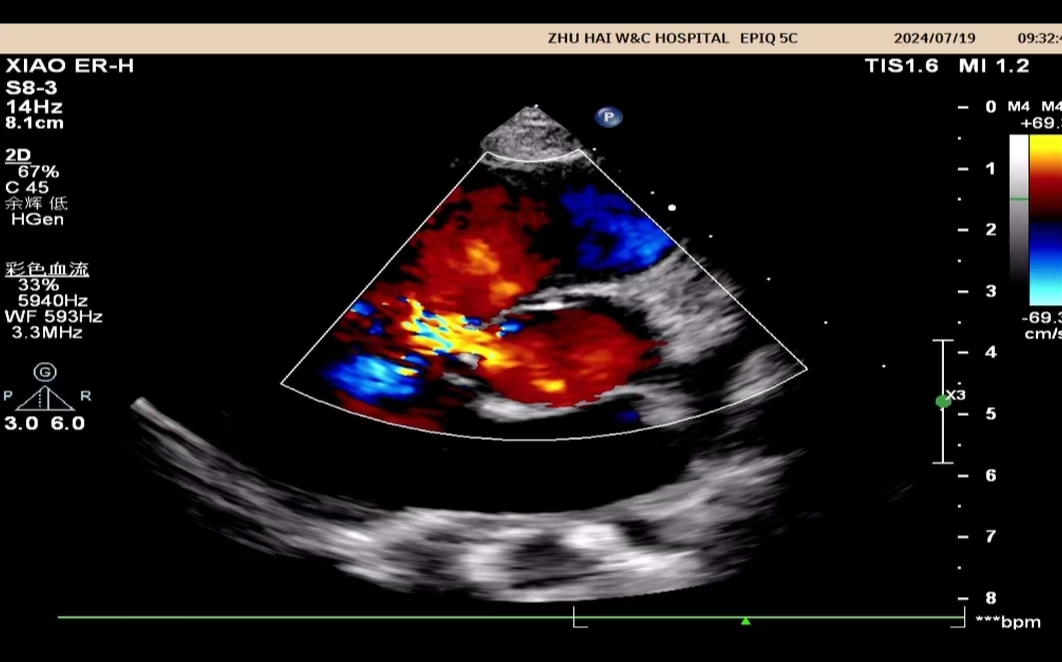

心脏彩超是能够动态显示心腔内部结构、心脏搏动和血液流动情况的一种无创性检查技术。通俗地说,心脏探头有点类似于摄像机的镜头,通过镜头的不断移动和变换,让心脏的各个结构得到准确的呈现,从而让医生能够根据这些图像判断心脏是否存在问题。

大部分都可以通过心脏彩超查出,例如:房间隔缺损,室间隔缺损,动脉导管未闭,心内膜垫缺损,法洛四联征、大动脉转位等。

心脏彩超除了对于先天性心脏病有比较好的显示效果外,对于后天因素所导致的心脏病,同样能够有很好的诊断效果。比如常见的瓣膜狭窄、瓣膜关闭不全、风湿性心脏瓣膜病、冠心病、肥厚型心肌病、扩张性心脏病等。